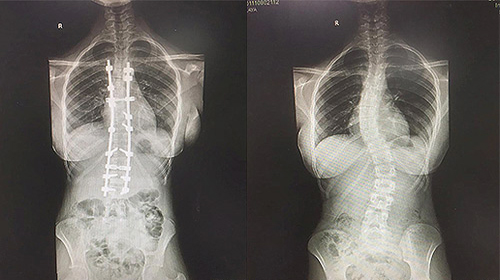

أنهى فريق طبي بمستشفى د. سليمان الحبيب بالعليا معاناة طفلة كانت مصابة بانحراف خلقي متطور في العمود الفقري «الجنف»، ونجح الفريق بقيادة د. واصف السباعي استشاري جراحة العظام والعمود الفقري في إجراء عملية معقدة استمرت زهاء الـ«6» ساعات، تمكن خلالها وبفضل من الله من تقويم العمود الفقري وتثبيت ودمج الفقرات للطفلة البالغة من العمر «12» عاماً.

وقال د. السباعي: إن الطفلة قدمت قبل نحو «8» أشهر إلى المستشفى برفقة ذويها وهي تشتكي من انحناء جانبي للعمود الفقري ومن تحدب وآلام في الظهر، إضافة إلى صعوبة في ممارسة الحياة الطبيعية، وفور وصولها إلى المستشفى أخُضعت لكافة التحاليل الطبية اللازمة، التي بينت إصابتها بحالة انحراف تزيد نسبته عن «40» درجة، وظلت منذ ذلك الوقت تحت الرقابة والمتابعة الطبية، إلى أن تأكد تزايد الانحراف، الأمر الذي حتم إخضاع الطفلة لعملية جراحية تم فيها تقويم العمود الفقري وتثبيت ودمج الفقرات، واستخدمت في العملية مجموعة من أحدث الأجهزة الطبية الأمريكية، التي ساهمت مع الكوادر الطبية عالية الكفاءة والتأهيل بمستشفى سليمان الحبيب بالعليا في إنجاح العملية بنسبة «100%»، وأضاف أن الطفلة بحالة صحية جيدة وتستطيع تحريك أطرافها بسهولة بعد مضي أقل من «24» ساعة من إجراء العملية، وتوقع أن تغادر الطفلة المستشفى في غضون «5» أيام شريطة أن تلتزم بالبرنامج العلاجي المصمم لها وبإرشادات الفريق الطبي المعالج.